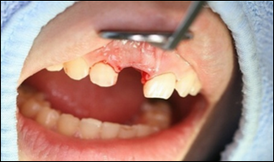

術前口腔内写真術前口腔内写真

歯が割れて唇側に傾いています。

術前口腔内写真

短い期間で治療を終わらせる為に、出来るだけ組織へのダメージを小さくするために最低限の傷口でインプラントの埋入を行いました。